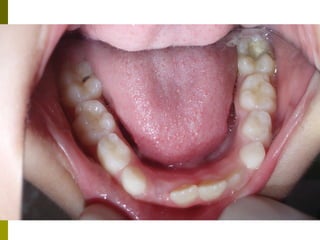

Πρώτη σχολική ηλικία 6-10 ετών

   Αρχίζει αλλαγή των τομέων και η ανατολή των

πρώτων μόνιμων γομφίων (μεικτή οδοντοφυΐα)

   Παρατηρούμε η αλλαγή δοντιών να γίνεται με τη

σωστή σειρά και στη σωστή θέση

   Μπορεί να χρειαστεί πρώιμη ορθοδοντική

θεραπεία, για να αποφευχθούν πιο δύσκολες και

πολύπλοκες εργασίες αργότερα

   Διατήρηση νεογιλών δοντιών στον οδοντικό

φραγμό μέχρι τη φυσιολογική τους απόπτωση